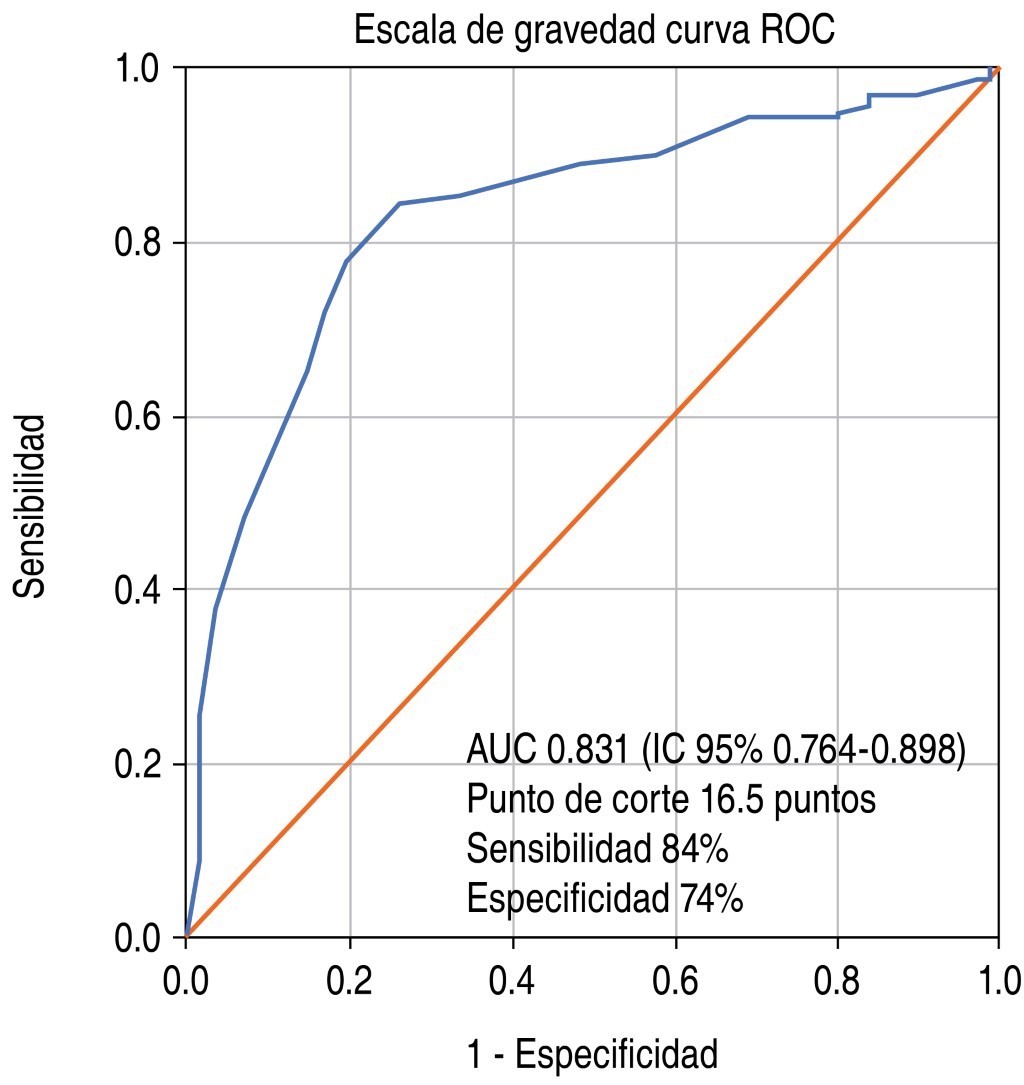

Escala tomográfica para evaluar la gravedad de COVID-19 en el Instituto Nacional de Enfermedades Respiratorias